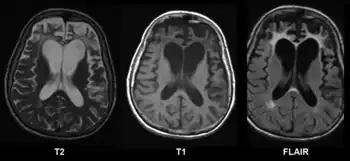

CT and MRI are most commonly used to observe the brain for cerebral atrophy. A CT scan takes cross sectional images of the brain using X-rays, while an MRI uses a magnetic field. With both measures, multiple images can be compared to see if there is a loss in brain volume over time.[20]

Cerebral atrophy can be hard to distinguish from hydrocephalus because both cerebral atrophy and hydrocephalus involve an increase in cerebrospinal fluid (CSF) volume. In cerebral atrophy, this increase in CSF volume comes as a result of the decrease in cortical volume. In hydrocephalus, the increase in volume happens due to the CSF itself.[20]

Typical imaging findings in normal pressure hydrocephalus versus brain atrophy.[21]